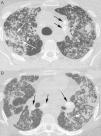

The high-resolution CT findings of silicoproteinosis consist of bilateral air-space disease manifesting as consolidation, ground-glass opacities, and centrilobular nodules. Punctate calcifications superimposed in areas of consolidation and calcified lymph nodes are commonly seen.3,4 (Fig. 1).

A 29-year-old man with silicoproteinosis. The patient was a sandblaster in the naval industry, with a history of exposure to silica of 2.8 years. CT scans of upper (A) and lower (B) lobes show numerous bilateral airspace nodules, some of them confluent (white arrows) with areas of consolidation in both lungs. Calcified mediastinal and hilar lymph nodes (black arrows) are also evident.